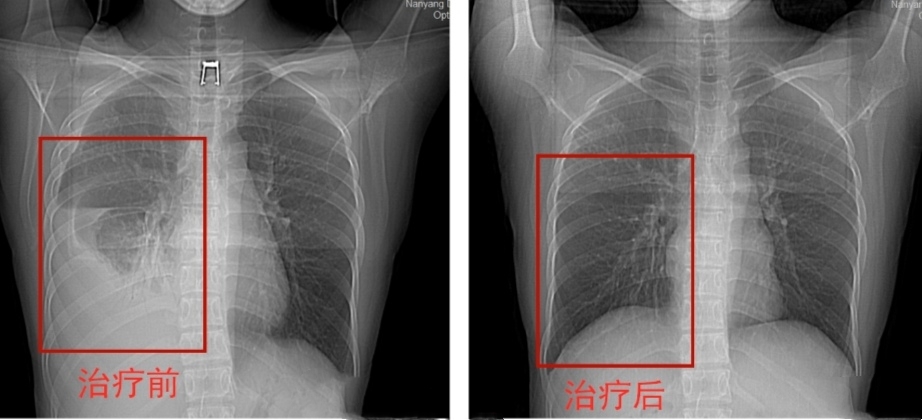

一个月前,新冠肺炎特殊的疫情,王先生因复工需要体检,就在户口所在地拍片,无意间被医生发现了胸腔积液,就建议他来南阳市第六人民医院做进一步检查,医生看了胸部CT,直接让他住院治疗,这可让王先生吓了一跳,他并没有感觉到像以前患病时的胸闷不适、咳嗽,只是偶尔出现活动后气急,这几年来,也没再做过任何检查,偶尔加重了便以为是感冒或者抽烟、年龄增加等原因,就自行在附近药店买些口服百喘朋及平喘止咳糖浆等治疗,怎么也没想到再次复发。带着诸多疑惑,王先生再次来到南阳市第六人民医院。

经过牛主任的详尽介绍,王先生对自己这次发病的原因终于明白了,原来是因为在没有完成疗程前就自行停药而引起的复发!所幸的是他的脓液经过几次的抽吸治疗后已大大减少,近日就可出院。可见,肺结核患者是不能轻易停药,如果盲目停药,病情有复发的可能,更会影响治疗的效果,浪费前边的治疗。他表示,这次一定会按照医生的要求正规治疗,遵从医嘱,按时吃药,切不可拿自己的生命和健康开玩笑!